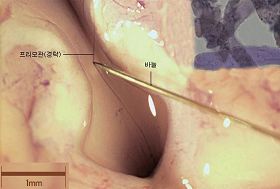

他们在连结兔子的大脑与脊髓的部位上发现了非常细的经络管道(Primo System,图一,针头尖指的头发状部位)。经络管是呈现着透明而纤细,没有染色无法观察到的细管。

在连结兔子的大脑与脊髓的部位上发现了非常细的经络管道